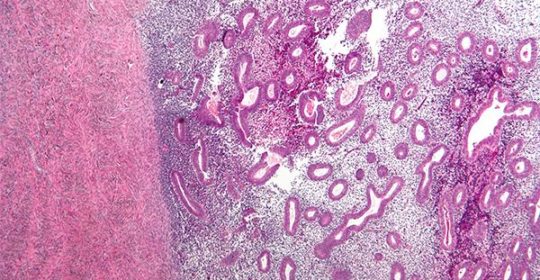

La endometriosis sucede cuando existen células del endometrio fuera del útero, es decir, no solamente en su lugar original. Este tejido es capaz de asentarse en cualquier otro lugar del abdomen como ovarios, intestino e incluso en lugares más lejanos como en los pulmones y origina sangrados en los períodos de menstruación, en el lugar que se encuentren estas células y origina un proceso inflamatorio que da lugar a adherencias entre órganos próximos y formaciones a modo de finas membranas.

A pesar de décadas de investigación sobre este tema, se desconoce cuál es la etiología de esta enfermedad y todavía no se tiene una explicación concreta de los motivos por los que no todas las mujeres la padecen. La endometriosis se clasifica en cuatro fases (I: mínima; II: leve; III: moderada; y IV: grave) en función de la ubicación, extensión y profundidad de los focos endometriósicos; la presencia y gravedad de las adherencias o “telillas”, la unión de órganos próximos por lesiones debidas al sangrado.